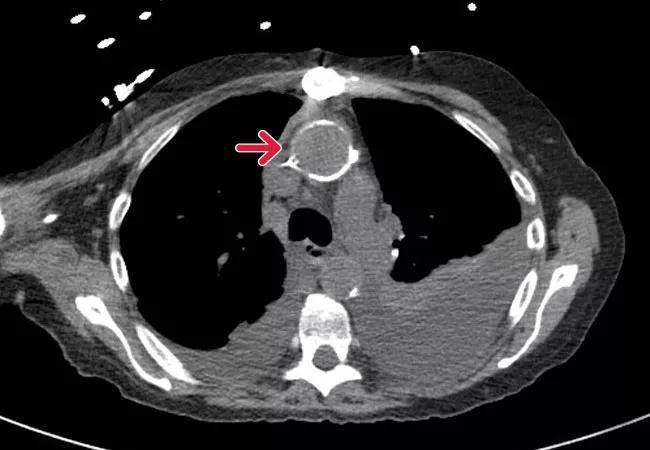

A noncontrast CT of the ascending aorta

A noncontrast CT of the ascending aorta (porecelain aorta) in a 58-year-old woman with a history of radiation-associated heart disease.